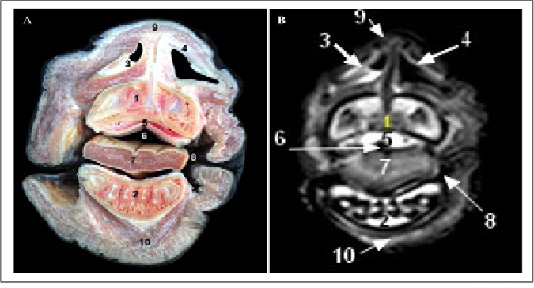

Cross sectional anatomy (Panel A) and MR image (Panel B) of horse head at the level of the diastema. 1) Ramus of mandible; 2) Nasal bone; 3) Concho frontal sinus (rostral part); 4) Fronto-maxillary opening; 5) Caudal maxillary sinus; 6) Dorsal nasal sinus (Caudal end of dorsal nasal concha); 7) Nasopharynx; 8) Soft palate; 9) Masseter muscle; 10) Pteyrgoid muscle (medial part).